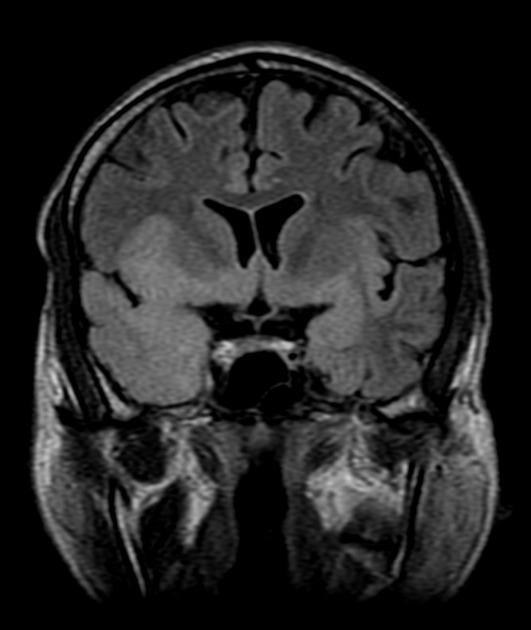

(б) МРТ, ДВИ, аксиальный срез: у двухнедельного ребенка с судорожным синдромом и выбуханием родничка визуализируется распространенное ограничение диффузии в области структур серого и белого вещества без четкой локализации ЕЯ. Были выявлены увеличение IgM и положительный результат ПЦР против ВПГ. ДВИ имеет большое значение в ранней диагностике этого состояния. (а) МРТ, Т2-ВИ, корональный срез: у младенца, у которого в перинатальном периоде был диагностирован ВПГ-2-энцефалит, определяются распространенная кистозная э нцефаломаля-ция с выраженным расширением боковых желудочков заместительного генеза.

Герпетический энцефалит у младенцев характеризуется более диффузным поражением, причем эти изменения сложнее заметить на фоне незавершенной миелинизации; поражение типично затрагивает кору полушарий, глубокие слои белого вещества, включая перивентрикулярные области и таламусы. Медиальные области височных и нижние области лобных долей часто интактны. Геморрагии встречаются реже и появляются в более поздних стадиях.

Сигнальные характеристики аналогичны энцефалиту у взрослых:

- области повышенного сигнала в Т2-взвешенных последовательностях могут быть плохо заметными на фоне незрелой миелинизации;

- МР-картина последствий перенесенного процесса включает зоны лейкомаляции, диффузную кистозную энцефаломаляцию и кальцификаты, расположенные диффузно либо по ходу извилин.